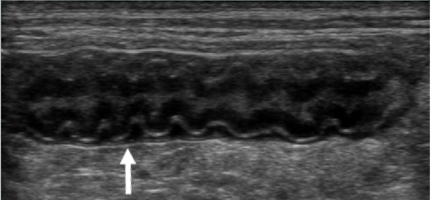

An advanced, highly practical ultrasound course designed to extend diagnostic capability, combining hands-on training in challenging abdominal structures, Doppler techniques and ultrasound-guided sampling for confident clinical application.

This course is suitable for you if you‘re a general practitioner who already has experience performing an abdominal ultrasound and would like to elevate your skills in evaluating the more challenging abdominal structures and at performing ultrasound-guided sampling. You’ll also learn how to use ultrasound for the assessment of the thorax (except heart) and neck, increasing the range of applications of this imaging modality that you can offer your patients. This two day Advanced Small Animal Ultrasound course will consist of a combination of lectures and several hands on practical sessions with the guidance of the course tutors.

- Become familiar with the normal appearance of lung and being able to identify thoracic wall, pleural, pulmonary and mediastinal disease using ultrasound